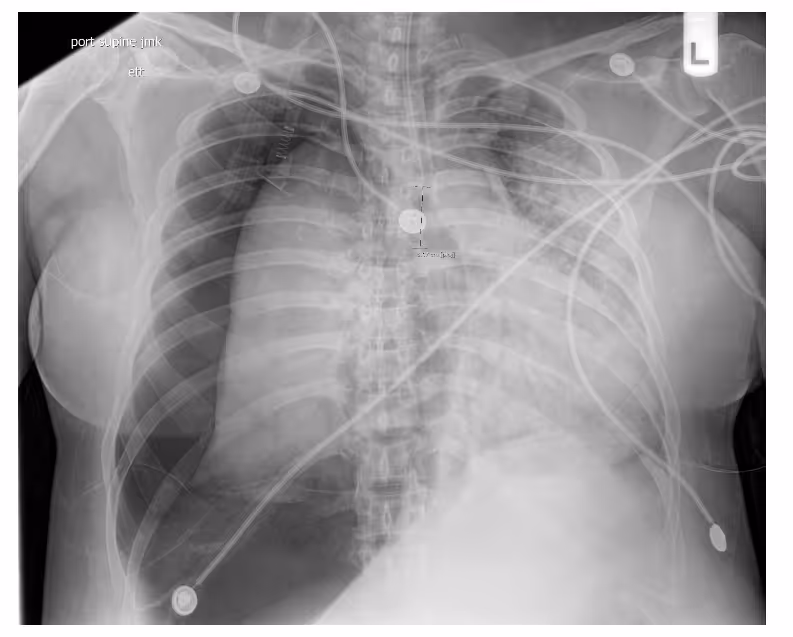

Ferrum Health partners with best-in-class AI providers offering solutions designed to reduce radiology workload and improve patient care.VinBrain Case Study: Accurate Analysis for ICU Patients - PneumothoraxIntroductionICU patients often have chest x-ray images taken at the bedside with a portable x-ray machine while many medical devices are placed on their bodies. This makes diagnosis more complex than a common patient.Clinical Case

- A 40-year-old female patient with post endotracheal tube placement with known COViD pneumonia

- Image findings:

- Interval placement of endotracheal tube terminating 3 cm from the carina.

- Large right tension pneumothorax and scattered lucencies are seen.

- The cardiomediastial silhouette is shifted into the left hemithorax, and the vasculature is obscured.

- Complete collapse of the right lung.

- Diffuse patchy airspace opacities in the left hemithorax

- No pleural, osseous, or soft tissue abnormalities

- The patient has many medical devices placed on their body, and more than one abnormal finding appears on the lungs.

- The patient was diagnosed with sizeable right tension pneumothorax, with a complete right lung collapse and a leftward shift of the cardiac mediastinal silhouette.